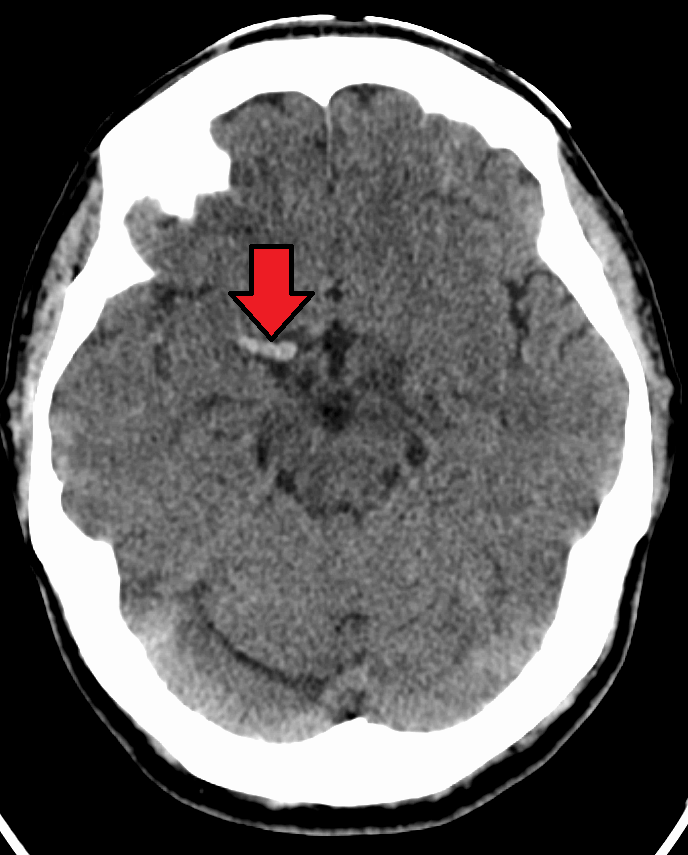

뇌정맥동 혈전증(CVST)은 경막정맥동이 혈전으로 막혀 발생하는 드문 형태의 뇌졸중이다. 증상으로는 두통, 시야 이상, 안면 및 신체의 한쪽 팔다리 쇠약과 같은 뇌졸중 증상 및 발작이 나타날 수 있다. 진단은 대개 CT 또는 MRI 스캔을 통해 이루어진다. 영향을 받은 대부분의 사람들은 완전히 회복된다. 사망률은 4.3%이다.[9]2. 1. 7. 해면 정맥동 혈전증

뇌정맥동 혈전증은 경막정맥동이 혈전으로 막혀 발생하는 드문 뇌졸중이다. 두통, 시력 이상, 한쪽 얼굴이나 팔다리 마비, 경련 등 뇌졸중으로 인해 나타날 수 있는 다양한 증상이 나타난다. 주로 CT나 MRI를 통해 진단한다. 대부분의 환자는 잘 회복되지만, 유럽 여러 나라와 멕시코의 보고에 따르면 사망률은 4.3%이다.